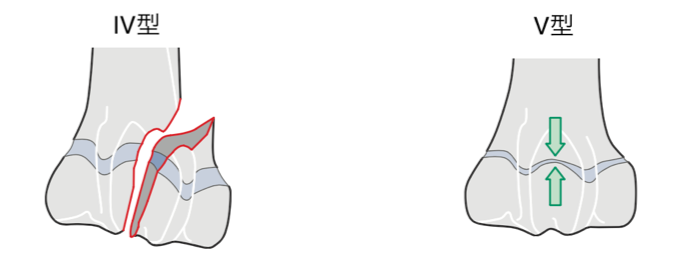

成長板骨折はSalter-Harris分類という分類方法により、下のようにⅠ〜Ⅴ型に分類されます。